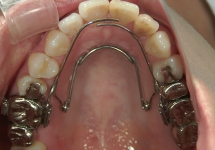

急速拡大装置(きゅうそくかくだいそうち)

2週間かけて、上顎の骨のつなぎ目を急速に広げる装置です。1日2回、中央についている拡大調節ネジを調整することで、強い力で歯列を押し広げます。永久歯に生えそろってから、あまり時間のたっていない20歳くらいまで効果がみられます。